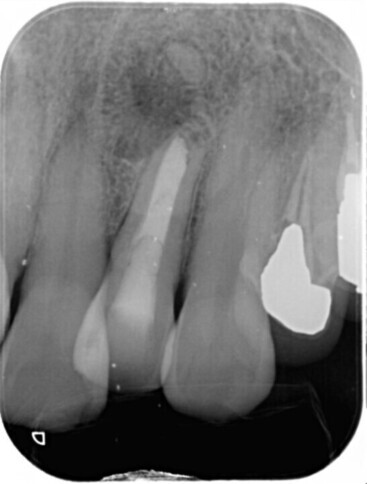

必要に応じてCT撮影を実施(根管形態の確認や病変の確認の為)

歯の根の形態は非常に複雑で、通常のレントゲンでは確認できない場合があります。CT撮影を行うことで、根管の本数や形、病変の広がりを立体的に把握し、的確な治療計画を立てます。